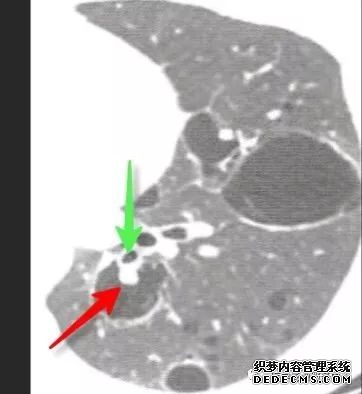

肺转移瘤的十种不典型CT表现